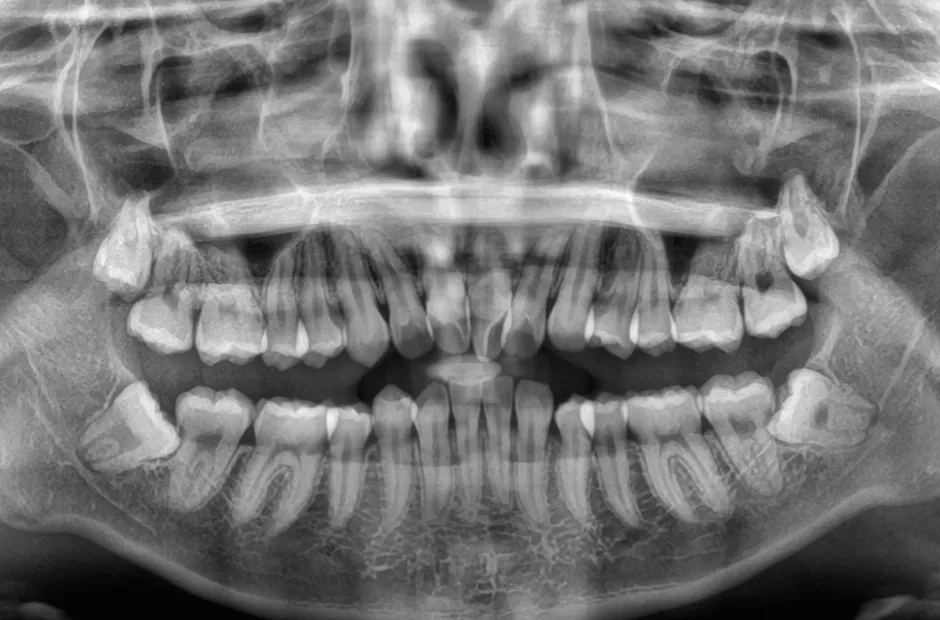

過剰歯

| 診断名・主訴 | でこぼこ |

|---|---|

| 年齢・性別 | 22歳・女性 |

| 治療期間・回数 | 1年6か月 |

| 治療に用いた主な装置 | リンガルブラケット |

| 抜歯部位 | 過剰歯 |

| 治療費 | 100万円(税抜) |

| リスク・副作用 | 装置による違和感・疼痛・歯肉退縮・歯根吸収・虫歯のリスクなど |

治療前

治療中

治療後